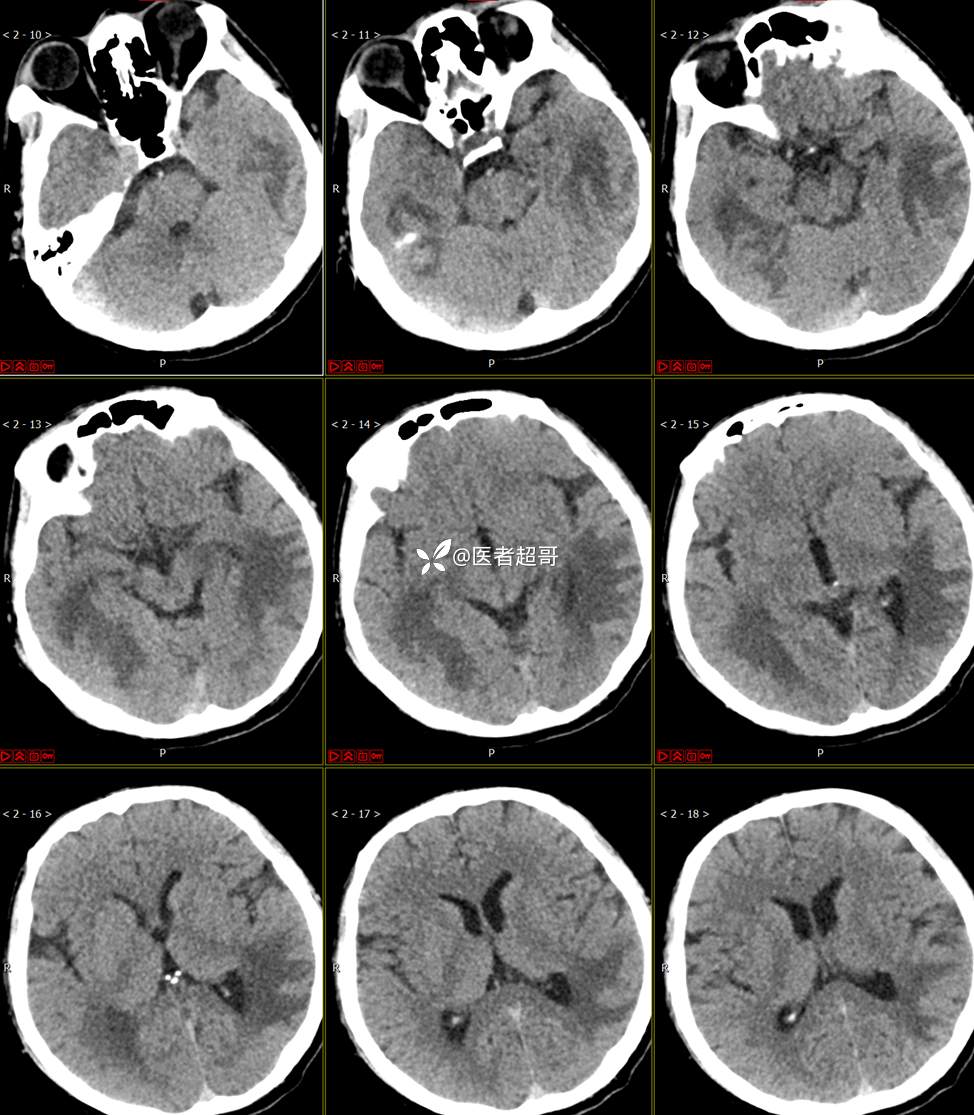

【影诊笔记773】头痛、头晕10天,CT、MRI齐全,请高诊!

主 诉:头痛、头晕10天

现病史:患者10天前无明显诱因感头痛、头晕,伴记忆力减退,无恶心、呕吐,无肢体抽搐及肢体活动不灵等,于我院就诊,行颅脑MR示颅内多发占位,现患者为求进一步治疗于我院就诊,以“颅内占位”收入我科。患者目前神志清,精神可,饮食、睡眠正常,体重无明显变化。

既往史:既往急性肝功能衰竭病史.